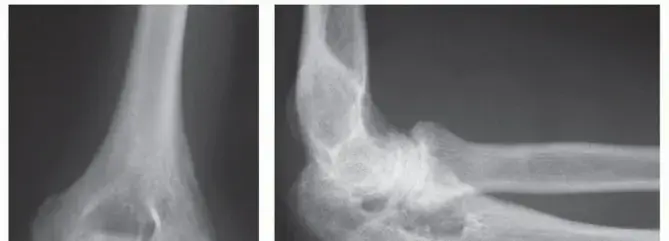

1. التهاب المفاصل الروماتويدي (Rheumatoid Arthritis - RA):

• ماهيته: هو اضطراب مناعي ذاتي مزمن، حيث يهاجم الجهاز المناعي للجسم عن طريق الخطأ الأنسجة السليمة، وخاصة بطانة المفاصل (الغشاء الزليلي).

• تأثيره على اليد: يُعد التهاب المفاصل الروماتويدي السبب الأكثر شيوعًا لتلف المفاصل السنعية السلامية (MCP). يؤدي إلى التهاب بطانة المفصل (التهاب الغشاء الزليلي) وتورمها، مما يؤدي بمرور الوقت إلى تآكل الغضروف والعظام وتلف الأربطة والأوتار المحيطة بالمفصل. يمكن أن يؤثر أيضًا على المفاصل السلامية القريبة (PIP)، ولكنه أقل شيوعًا.

• أعراضه الجهازية: لا يقتصر تأثيره على المفاصل، بل يمكن أن يسبب أعراضًا جهازية مثل التعب الشديد، آلام العضلات، فقدان الشهية، الاكتئاب، فقدان الوزن، فقر الدم، وضعف الجهاز المناعي بشكل عام.

• الضعف: قد يشعر المريض بضعف في قوة القبضة أو صعوبة في حمل الأشياء.

• تشوهات المفاصل: مع تقدم المرض، يمكن أن تتغير المفاصل في شكلها، فتظهر عليها نتوءات عظمية أو انحرافات في الأصابع (مثل الانحراف الزندي في الروماتويد، أو تشوهات عنق البجعة أو العروة في الأصابع).

• المفاصل السنعية السلامية (MCP): وهي براجم اليد، غالبًا ما تستبدل في حالات التهاب المفاصل الروماتويدي.

• المفاصل السلامية القريبة (PIP): وهي مفاصل منتصف الأصابع، تستبدل في حالات الخشونة أو التهاب المفاصل الصدفي أو الروماتويدي.